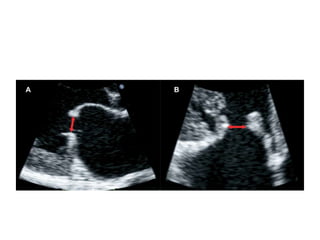

2D ECHO/PLAX/RHEUMATIC

• Valve domes in diastole

due to commissural fusion

• Leaflet thickening

beginning at the edges of

the leaflets

• Produces significant

narrowing of orifice

• Fibrosis, thickening

and shortening of

chordae common

• Calcification may also

progressively involve

chordae